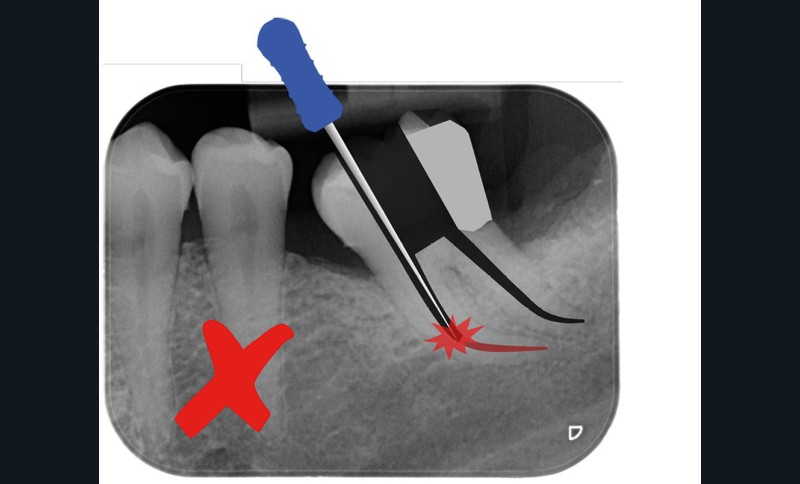

Trop petite

Une cavité d’accès trop petite [2] optimiserait le pronostic biomécanique (préservation dentaire maximale) mais pourrait compromettre le pronostic endodontique : mauvaise lecture de l’anatomie, instrumentation partielle, non ergonomique et avec risque de fracture, défaut de nettoyage des parois canalaires [3], irrigation inadéquate, difficulté d’obturation canalaire, voire d’obturation coronaire. Ce sera le cas des cavités d’accès « Ninja » [4] ou ultraconservatrice (fig. 1), des cavités d’accès « Truss » [5] (fig. 2), des cavités d’accès dites « opportunistes » [6] (fig. 3).